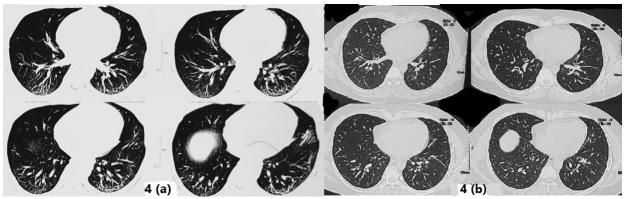

酷似间质性肺疾病的新冠后综合征:病例系列

Long COVID Mimicking Interstitial Lung Disease: A Case Series.

Interstitial lung diseases (ILD) can occur due to various known or unknown causes. They usually present with dry cough and exertional dyspnea. On radiology usual findings are ground glass opacities (GGO's), reticular shadows, nodules etc. Some patients after acute COVID-19 (coronavirus disease 2019) suffer from persistent symptoms/manifestations. These have been called 'Long COVID'. Long COVID also has radiological features like GGO's, nodules and reticulations. Further, patients even without history of acute COVID-19, can also present with 'Long COVID'. In the present case series, we describe three such cases with no history of having suffered from COVID-19, presenting with ILD like features and diagnosed as Long COVID. We infer from these cases that 'Long COVID' can both clinically and radiologically mimic ILD's. Hence, emphasizing the fact that in the present COVID-19 pandemic situation, 'Long COVID should be a differential diagnosis to be considered while making a new diagnosis of ILD.

摘要

间质性肺疾病(ILD)可由各种已知或未知原因引起。它们通常表现为干咳和劳力性呼吸困难。在放射学上,常见表现为磨玻璃影(GGO)、网状阴影、结节等。一些急性新型冠状病毒肺炎(COVID-19,冠状病毒病2019)患者会出现持续症状/表现。这些被称为“长新冠”。“长新冠”也有放射学特征,如磨玻璃影、结节和网状影。此外,即使没有急性COVID-19病史的患者也可能出现“长新冠”。在本病例系列中,我们描述了3例无COVID-19病史、表现出ILD样特征并被诊断为“长新冠”的病例。我们从这些病例中推断,“长新冠”在临床和放射学上都可能酷似ILD。因此,强调在当前COVID-19大流行情况下,“长新冠 ”应作为新诊断ILD时需考虑的鉴别诊断。